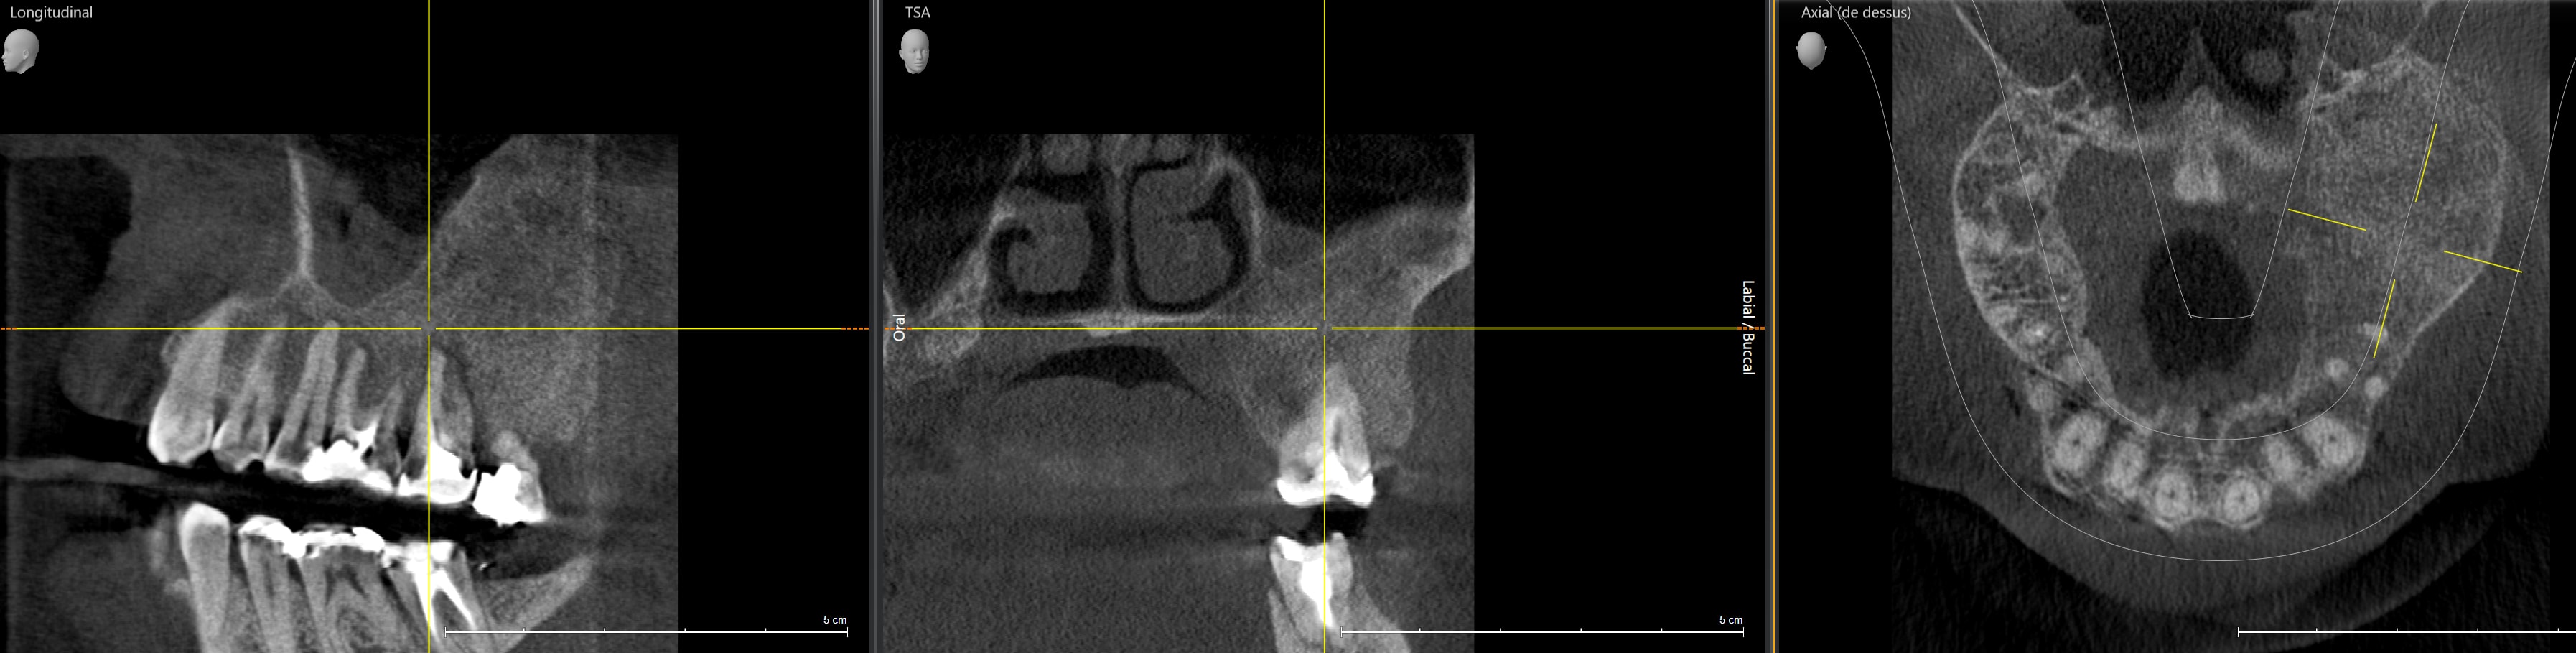

Une dissymétrie au niveau des processus alvéolaires me choque.

Cone beam.

Il y a quand même beaucoup d'os à gauche.